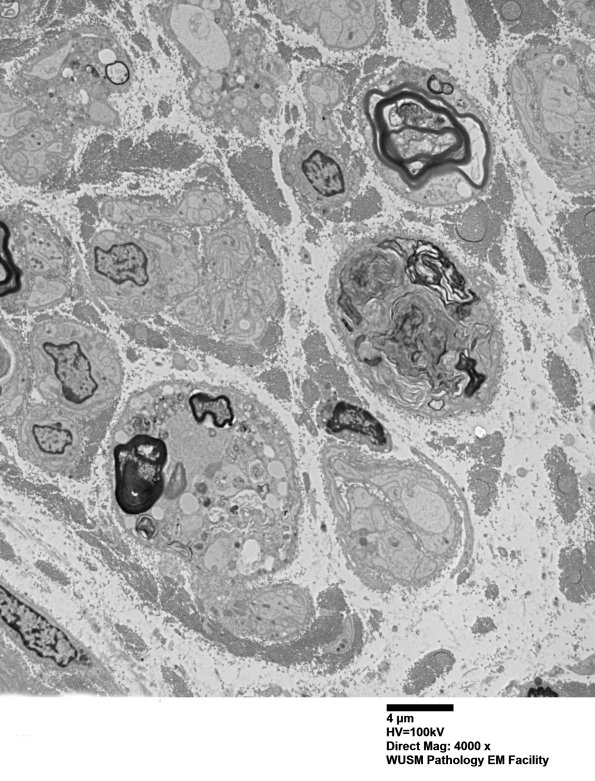

2F1,2 Low magnification view showing the loss of normal structures and the variation in appearance from one degenerating axon to another